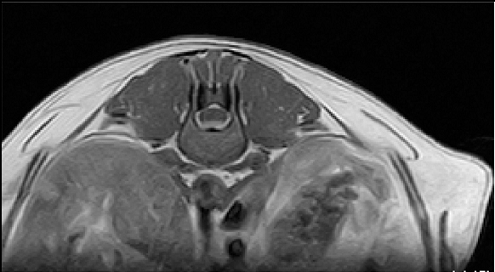

【画像診断】~ダックスフンド、雄10歳、グレート3の椎間板ヘルニア~

▲椎間板ヘルニアがあるMRI像、T13-L1の尾側像、造影後のT1強調画像(キャミックに依頼)

▲椎間板ヘルニアがあるMRI像、T13-L1の造影なしのT2強調画像(キャミックに依頼)

はい、たいへん有効です。その椎間板ヘルニアの起こっている部位や、左右どちらに起こっているか、その他の異常(合併症等)があるかもこの検査で調べます。脊椎の診断はMRI検査が最も理想的な検査法ですが、撮影時間や費用、設備の有無等に制約があるます。より実用的な検査としてはCTも良い検査法になりますが約15%でその部位に石灰化が起こってないとわらない場合がありますが、そんな場合は造影をすれば判定できます。MRIの場合、椎間板の変性はT2強調像、矢状断面像で最も良く観察、でき脊髄腫瘍、椎体腫瘍等、脊髄髄内の検出にも理想的な検査です。多くの腫瘍はT1強調像では脊髄と比較すると等信号から低信号にT2強調像では高信号となります。